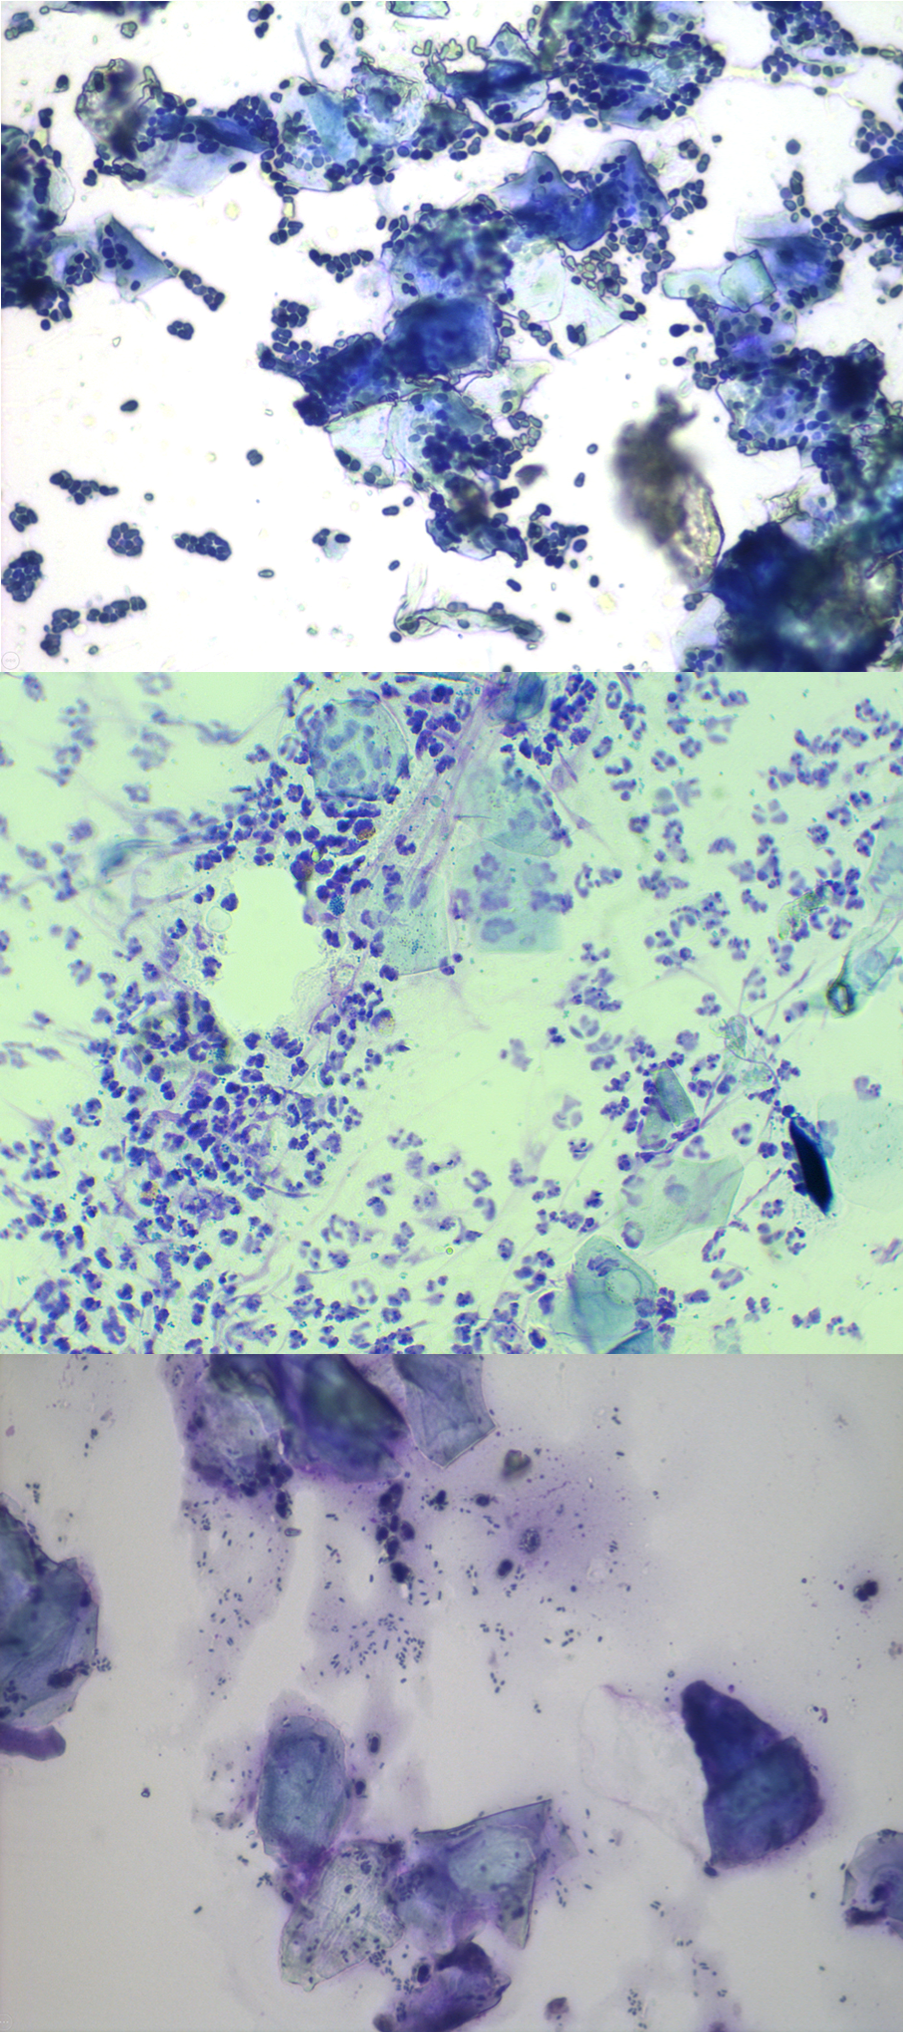

Dessa bilder visar olika stadier och typer av öroninflammation.

Nästa starkt rekommenderade steg i undersökningen är att ta ett prov på det sekret som finns i hundens öra och studera det under mikroskop, en så kallad cytologisk undersökning eller cytologi.

Det är ett snabbt och enkelt test som kan utföras på veterinärkliniken och med vars hjälp veterinären kan se om det finns onormala mängder bakterier eller jästsvampar i örat.

Med en cytologiborste, bomullspinne eller kanske ett behandskat finger samlas sekret från hundens öra in och stryks ut på ett objektglas. Provet färgas med ett särskilt färgämne för att veterinären ska kunna undersöka vad som pågår i hundens öra på mikroskopisk nivå. Där kan man se om det finns en överväxt av bakterier eller jästsvampar och leta efter inflammatoriska celler, som annars är osynliga för det mänskliga ögat.

Med en cytologiborste, bomullspinne eller kanske ett behandskat finger samlas sekret från hundens öra in och stryks ut på ett objektglas. Provet färgas med ett särskilt färgämne, för att veterinären ska kunna undersöka vad som pågår i hundens öra på mikroskopisk nivå. Där kan man se om det finns en överväxt av bakterier eller jästsvampar och leta efter inflammatoriska celler, som annars är osynliga för det mänskliga ögat.

Cytologi gör det inte bara möjligt för din veterinär att välja en lämplig initial behandling, utan det är också bra att upprepa undersökningen när hunden kommer på återbesök, för att se hur behandlingen fungerar, om den behöver förändras på något sätt och för att ta fram en långsiktig plan för hundens öronproblem.